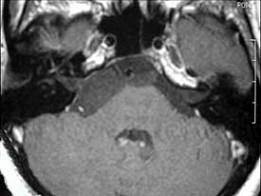

男,42岁,右侧听力下降,MRI检查如图,最可能的诊断为()A.表皮样囊肿B.听神经瘤C.三叉神经瘤D.脑膜瘤E.脑梗死

问题 男,42岁,右侧听力下降,MRI检查如图,最可能的诊断为()

选项 A.表皮样囊肿 B.听神经瘤 C.三叉神经瘤 D.脑膜瘤 E.脑梗死

答案 A